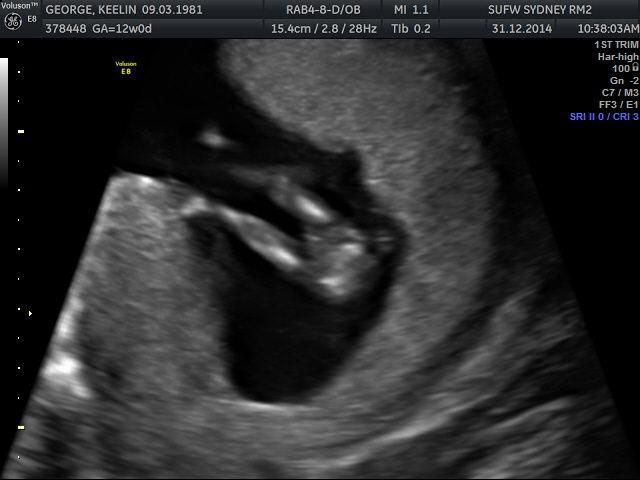

Looks like a girl nub to me but I think it's too early to tell from the potty shot

Leaning girl too, but as mentioned you'll need another couple of weeks before we can use a potty shot.

Thanks everyone I am very much hoping for a little girl..I had no idea about the 'potty shots' and didn't know what to make of it so thanks for letting me know its a bit early to tell